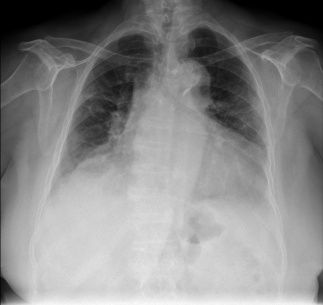

Image

Ground Truth

Base Model

Fine-tuned Model

Radiological signs of COPD.

Heart size, mediastinal, and hilar contours are normal. Lungs are hyperinflated with attenuation of pulmonary markings in the upper lobes, consistent with emphysema. No focal areas of consolidation are present within the lungs. There are no pleural effusions or pneumothoraxes.